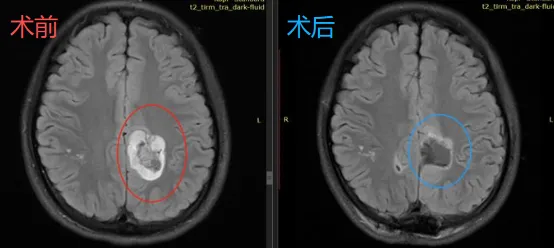

为确保手术安全,艺文一家最终决定前往德国国际神经科学研究所(INI)接受治疗。令人欣慰的是,手术过程十分顺利,术后磁共振显示肿瘤已被完整切除。